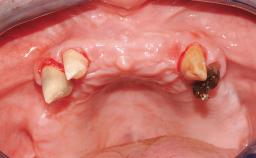

A 35-year-old Caucasian female presenting with advanced periodontal disease involving both the maxillary and the mandibular dentition was referred for evaluation. The patient, a non-smoker in good general health, requested treatment for recurrent periodontal abscesses, tooth mobility, and discomfort during chewing, as well as restoration of her missing teeth with a fixed prosthesis to improve mastication and esthetics. All residual maxillary teeth exhibited plaque deposits, deep pockets, bleeding on probing, and class III mobility and were evaluated as hopeless. All residual mandibular teeth except tooth 37 could be maintained after periodontal therapy.

Case Type Edentulous Maxilla

Area Full-Arch

# of Teeth All

# of Implants 8

Defining Characteristics Fully edentulous upper jaw to be rehabilitated with four or more implants